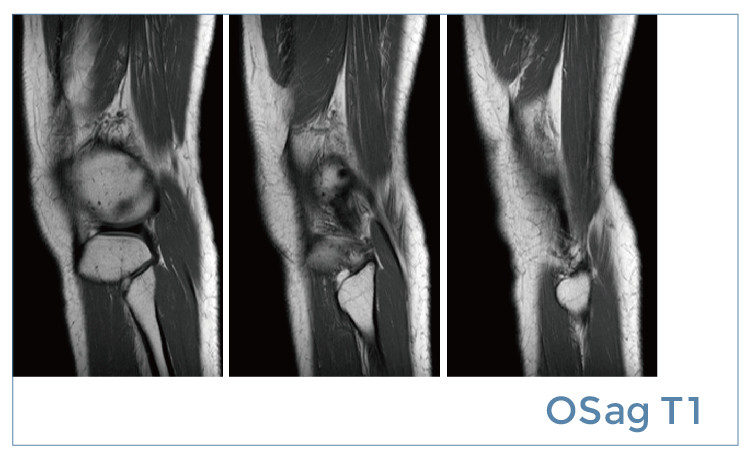

【朗润影像档案】磁共振影像病例分享(编号20190510)